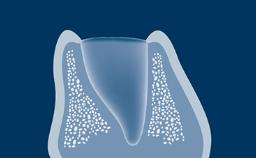

Tissue Integration of Dental Implants

Timing of Implant Placement after Tooth Extraction

Healing of the Extraction Socket